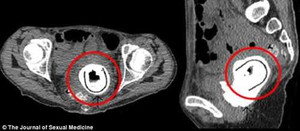

Người đàn ông Đài Loan (30 tuổi) cố chịu đau trong 2 ngày mới chịu đến khám bác sĩ để lấy đồ chơi tình dục mắc kẹt trong bàng quang.